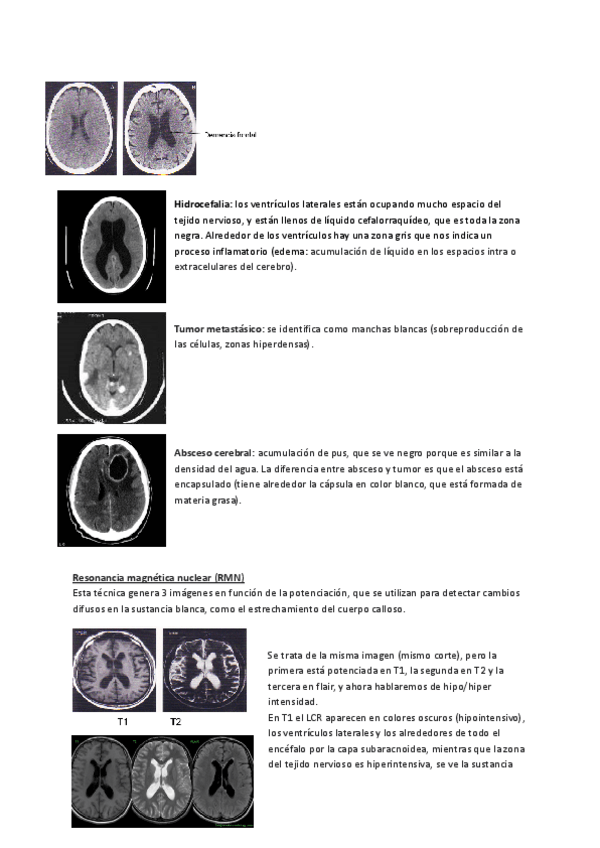

Práctica Autoformativa de técnicas de neuroimagen, es un cuadro comparativo que puede ser útil para estudiarlas. Incluye imágenes de como se ven cada una